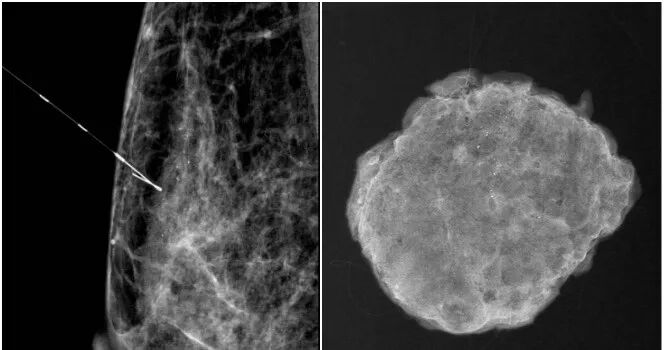

但临床未触诊到明显肿块,彩超也无法准确发现病灶,手术定位非常困难,贾海明医生与放射科张海容副主任医师讨论后,决定为李女士进行术前钼靶引导下钙化灶细针穿刺定位,帮助乳腺外科手术医生确定手术部位及范围。

张海容医生复阅钼靶片,确定目标病灶与体表的位置关系,在顾莉技师、聂玉霞技师协助下,在特定夹板引导下确定好穿刺位置,再根据定位位置及方向,将乳腺定位针穿刺到达病灶边缘,摄片确定定位针与目标病灶一致后释放导丝,确认导丝远端倒钩打开并固定于乳腺组织内。

待拍摄内外侧位片证实导丝前段与目标位置一致,剪掉体外多余钢丝并予敷料封贴固定、包扎后,李女士被送往手术室。

术中精准切除

乳腺外科贾海明医生在钼靶X线导丝定位下,完整精准切除病灶。